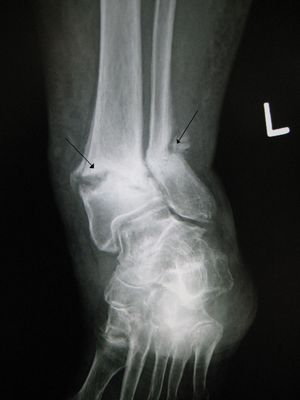

- 발목 골절

- 족관절 과부 골절

골절은 병력 청취 및 신체 검사를 통해 진단할 수 있다. 진단을 확인하기 위해 종종 방사선 영상 검사를 시행한다.[1] 특정 상황에서는 탈구 및 골절-탈구를 배제하기 위해 인접 관절의 방사선 검사가 필요하다.[1] 투사 방사선 촬영술만으로는 불충분한 경우, 컴퓨터 단층 촬영(CT) 또는 자기 공명 영상(MRI)이 필요할 수 있다.[1]